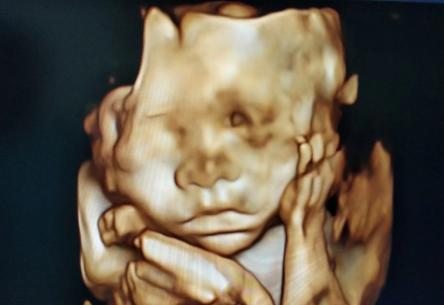

四维彩超是比较能看清楚胎儿样貌的检查,因此很多孕妇富强妈试图从四维的检查结果中找到关于孩子孩子的蛛丝马迹,那么怎样从四维彩超的结果上看出怀的是孩子还是孩子呢?小编总结了一些已生宝妈根据四维结果总结出生孩子的诀窍,当然这些是网友自己总结的并没有经过医学证明,孕妇富强妈可以对照看一下,但是具体结果还是要等到生产之后才知道。

四维彩超看孩子孩子的秘诀大全